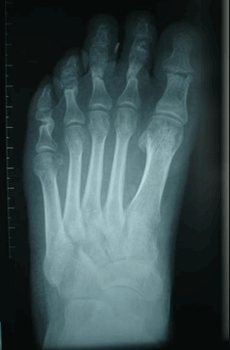

Caso 2: Hallux Valgus del Adolescente

Pie Izquierdo operado